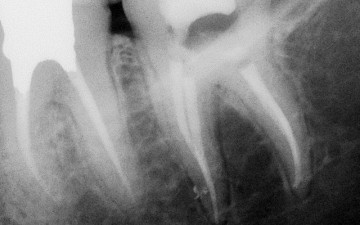

Pr K. BALTO, Saudi Arabia 1/3 Preoperative X-ray: tooth n°18 with irreversible pulpits and symptomatic apical periodontitis.